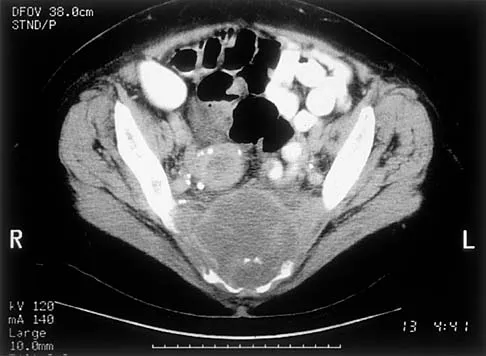

A 51-year-old male truck driver has had progressive left hip pain for more than 2 years, and he reports that the pain has become severe in the past 9 months. He is now unable to work because of the pain. Examination reveals that range of motion of the hip is limited to 95 degrees of flexion, 0 degrees of internal rotation, and 20 degrees of external rotation. The plain radiograph, MRI scan, and intraoperative gross photographs are shown in Figures 9a through 9d. Management should consist of